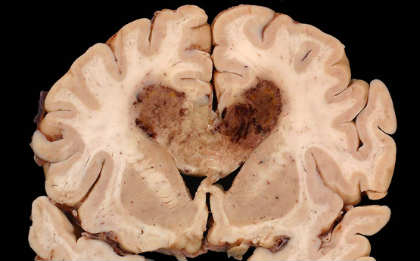

Mischel and colleagues, including Webster K. Cavenee, PhD, and Frank B. Furnari, PhD, of the Ludwig Institute and the UC San Diego School of Medicine, investigated the behavior of glioblastoma multiforme (GBM), the most common malignant primary brain cancer in adults. More than 9,000 new cases of the disease are diagnosed each year in the United States and effective treatments are limited. The tumors are aggressive and resistant to current therapies, such as surgery, radiation and chemotherapy. The median survival rate for newly diagnosed GBM patients is just 14 months.

GBM is characterized by a mutated variant of the epidermal growth factor receptor known as EGFRvIII that is found on extrachromosomal DNA in cancer cells. EGFRvIII promotes tumor growth. Some new drugs kill cancer cells by specifically suppressing or inhibiting EGFRvIII, but lose effectiveness as drug resistance soon develops.

Image Source: The image is adapted from the UCSD press release.